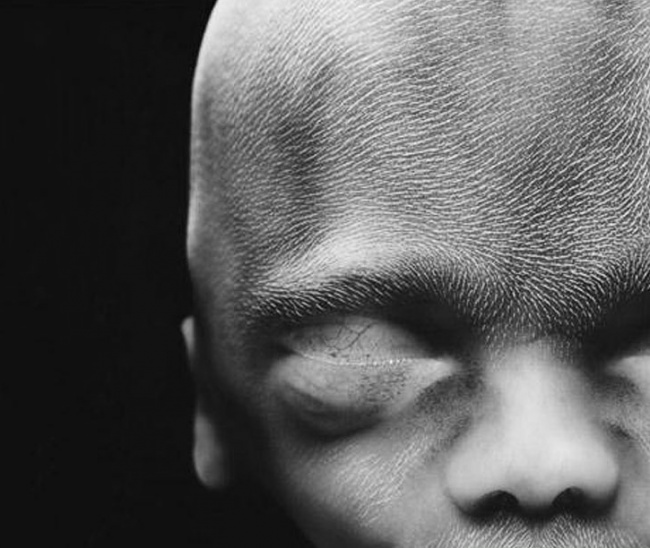

15 After 16 weeks

16 Fetus using its hands to explore its own body and surroundings

17 The skeleton, mainly consisting of flexible cartilage and a network of blood vessels, is visible through the skin

18 After 18 weeks